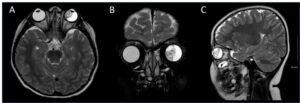

Вначале будет проведен осмотр и сбор жалоб, на основании которых врач продолжит диагностику с использованием лабораторных и инструментальных способов. МРТ и КТ позволяют визуализировать пораженный участок мозга, определить точное расположение опухолевого очага, его размеры, степень распространения, состояние окружающих тканей. Заключительным этапом диагностики является биопсия, цель которой состоит в подтверждении диагноза, получения сведений об особенностях опухоли. На основании всех результатов в Тель Авив Медикал Центр подбирается персонализированная программа лечения, которая обычно включает в себя комплекс таких мер: